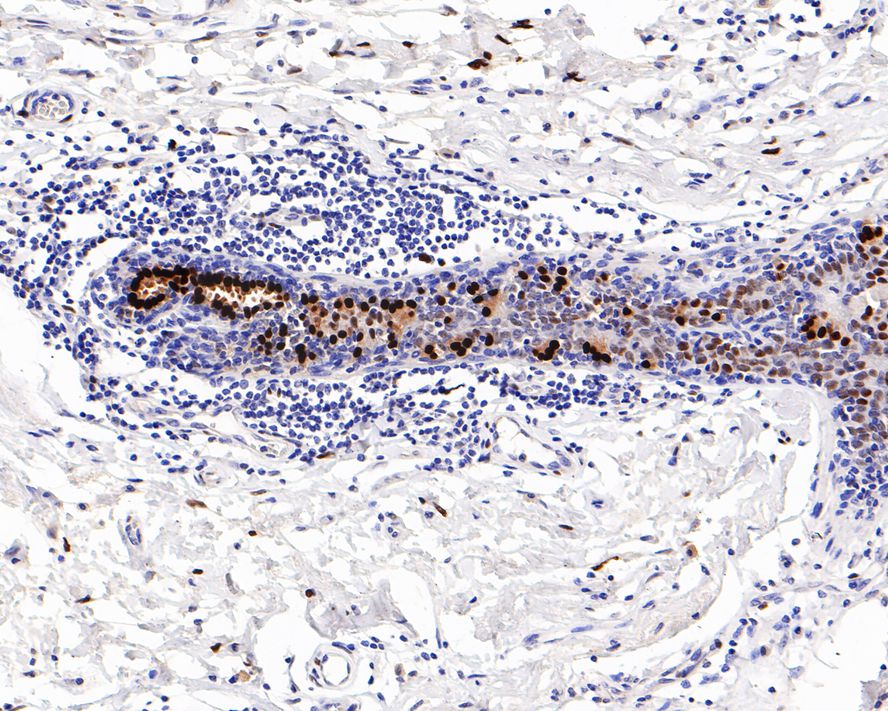

Catalog# HA721140

Estrogen Receptor alpha Recombinant Rabbit Monoclonal Antibody [PD00-04]

Application

IHC-P

Reactivity

Human